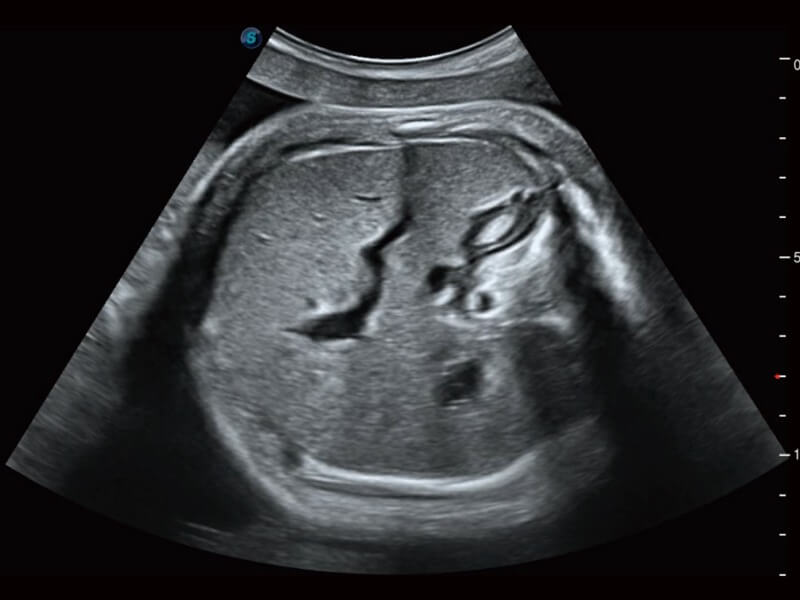

Die Visualisierung des 3D-Gesichts des Fetus ist wichtig für die Diagnose von Gesichtsanomalien. Durch Auto Face können Hindernisse und Artefakte wie Nabelschnur, Plazenta, Gebärmutter und Extremitäten einfach entfernt werden, um eine optimale Ansicht des fetalen Gesichts zu erhalten.

Basierend auf einem verlässlichen Deep-Learning-Algorithmus für Big Data ist S-Fetus eine brillante Komplettlösung für automatische Standard-Ebenen-Erfassung und Messung. Mit nur einem Klick werden gängige fetale Biometrie-Ergebnisse mit hoher Intelligenz, Genauigkeit und Effizienz erzielt, um einen beispiellosen Bedienungskomfort zu gewährleisten.

Dank der Unterstützung von Auto OB wird eine schnelle und hoch effiziente fetale Biometrie erreicht. Gleichzeitig kann diese auf Deep Learning basierende Methode zu konsistenteren Ergebnissen führen und die Variabilität, die vom Anwender abhängig ist, effektiv reduzieren.